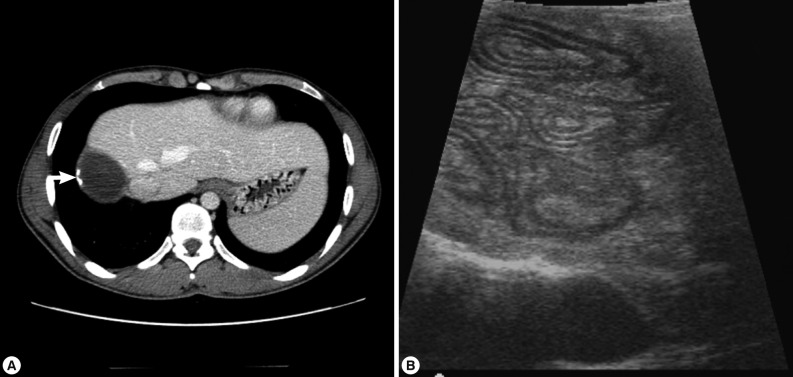

A 25-year-old Uzbek male was referred to the Department of Surgery, Dongsan Medical Center, Daegu, Korea on 8 January 2012, due to a cystic mass in the liver which was found by computed tomography at a private clinic. He had complained of right upper abdominal pain for 20 days. He has been in Korea for 3 years as a worker. Dull abdominal pain had progressed in its intensity day by day. He had no history of past illness and denied any contact history with domestic animals or pets as well as livestock in Uzbekistan. On physical examination, icterus was absent, and mild tenderness was recognized in the right upper abdomen without any palpable mass. He showed normal ranges of hemoglobin, white blood cell counts, including eosinophils, electrolyte profiles, and chemistry, including liver enzymes and bilirubin. His tumor markers, alpha-fetoprotein, carcinoembryonic antigen, and carbohydrate antigen 19-9, were within normal limit. CT from a private clinic recognized a 10×9 cm-sized hypoattenuating mass with focal wall calcifications at the liver segment 7 (

Fig. 1). Ultrasound examinations observed an oval and well-encapsulated echogenic mass with internally compactly filled tubular structures in the subcapsular location of the right posterior liver. MR image showed an oval mass with heterogeneous contents and without further contrast enhancement of this mass after intravenous administration of MR contrast (Primovist®; Bayer HealthCare, Seoul, Korea). Serologic test by ELISA to detect specific antibodies to parasite antigens, including

He underwent hepatic segmentectomy (Segment 7). On intraoperative ultrasound, these tubular contents were more clearly visualized (

Fig. 1). Grossly, the right hepatic mass showed a relatively well-demarcated, round, pale tan to red, smooth and cystic appearance, measuring 10.5×8.7×4.2 cm and 163.5 g. The cut-surface of the right hepatic mass showed a large unilocular cyst, containing olive-colored soft and flabby membrane attached with several small spherical brown clayish and soft nodules (

The cystic mass of the present case was diagnosed as CE based on images and histopathologic findings. His CT findings recognized a spherical cyst with calcification in the right liver segment 7. The ultrasound images visualized little fluid in the cyst but folding materials showed an image of so-called "ball of wool" (

Fig. 1). The image was compatible with that of the stage CE4 [

Fig. 1Radiologic findings. (A) Preoperative axial contrast-enhanced abdominal CT scan shows an oval, hypoattenuating mass, like cystic mass, with small wall calcifications (arrow). (B) Intraoperative ultrasound shows clear delineation of tubular structures, so-called "ball of wool" appearance.